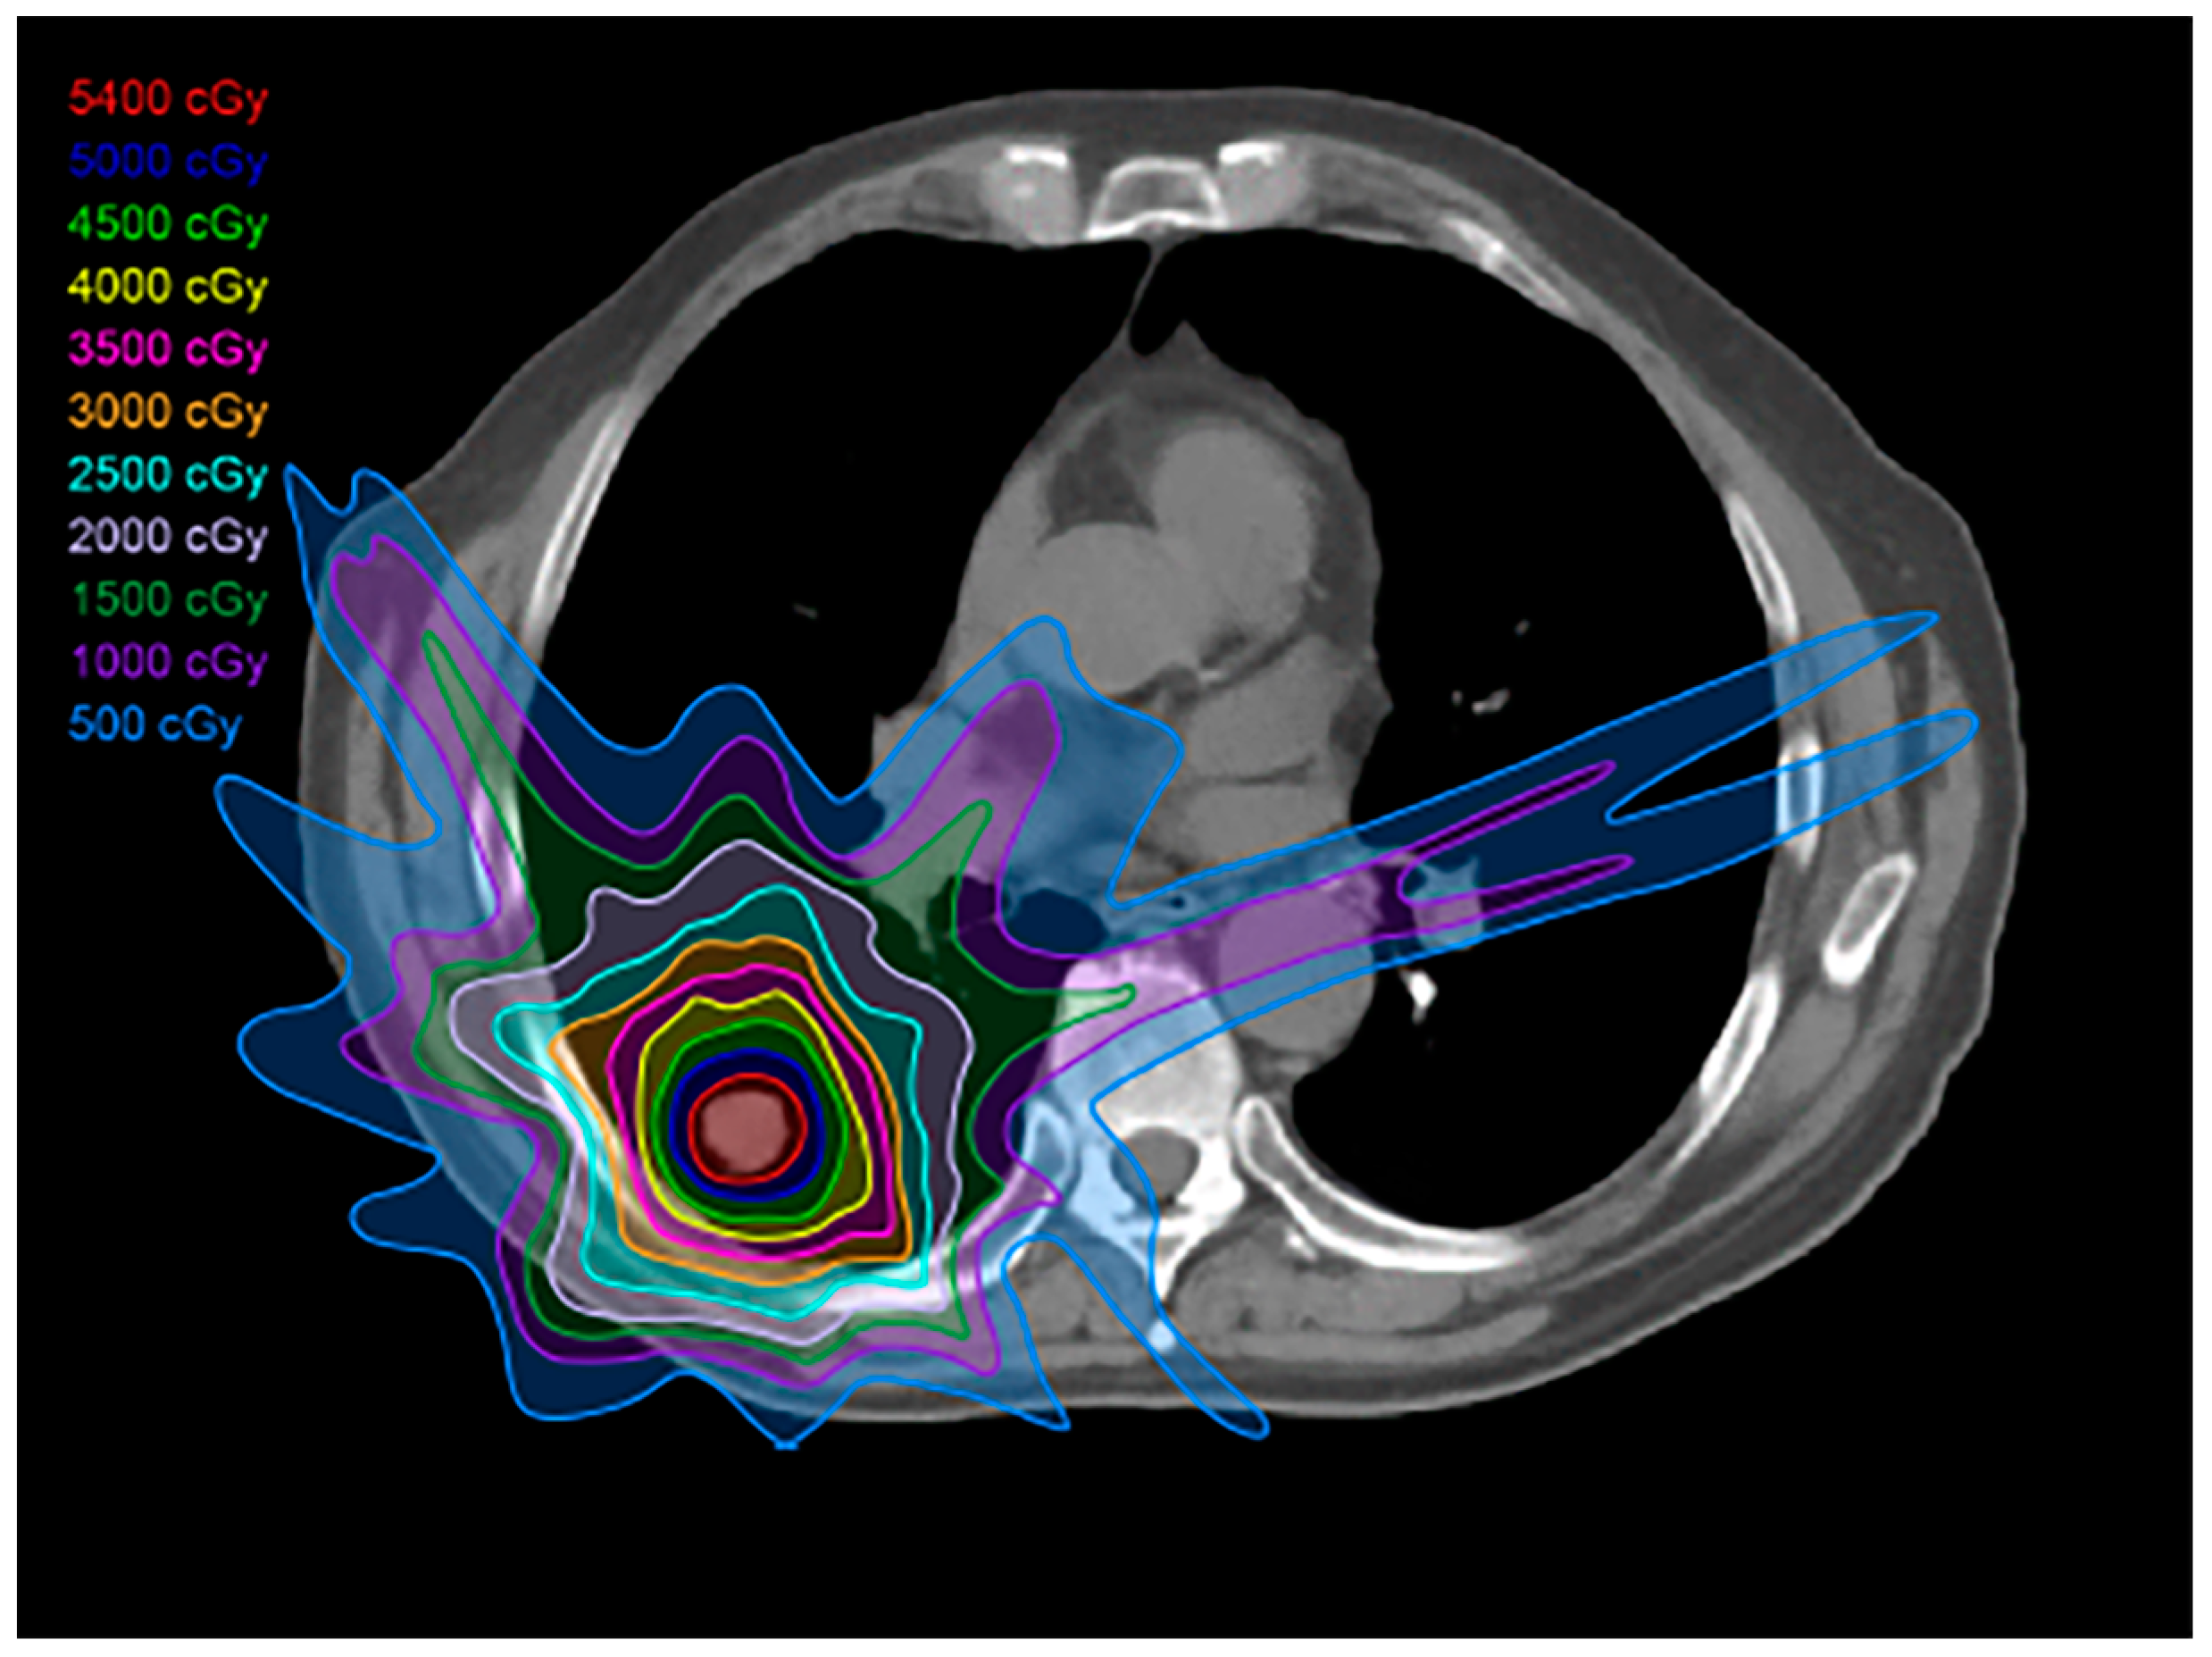

2.2. Three-Dimensional Conformal Radiotherapy

2.3. Intensity-Modulated Radiotherapy